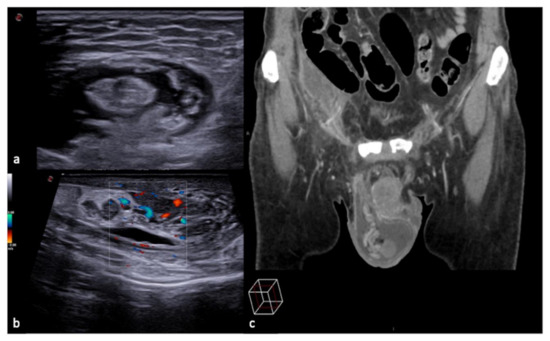

3.4. Anatomy and Anatomical Variants

Some anatomical structures and variances might yield difficult-to-interpret pictures, which can lead to errors if not fully understood [6]. The most insidious in emergency situations are pseudo-splenic hematoma (Figure 16 and Figure 17), pseudo-collections of pleural, pericardial, peritoneal, and retroperitoneal fluids (Figure 18, Figure 19, Figure 20 and Figure 21), and pseudo-pneumothorax related to abolished lung sliding due to the lung pulse or to patient apnea [6,7]. Others, such as hypertrophy diaphragmatic pillar (Figure 22), bladder pseudo-masses (Figure 23), inguinal pseudo-hernias (Figure 24), and the rouleaux phenomena, are generic, random, and highly conditioned (Figure 25). Often it is the emergency condition of the clinical context itself as well as the traumatic accident that could influence interpretational doubts or over-diagnosis with the necessity of more diagnostic confirmations, involving more costly complex examinations, an increased waiting time for the final diagnosis and medico-legal disputes [3,13].

Figure 24. Longitudinal US B-mode (a) and color-Doppler (b) scan of the inguinal canal show a blockage of the inguinal canal misinterpreted as an inguinal hernia with congested intestinal loop. On CT scan (c) it appears to be a right epididymitis with funiculitis.